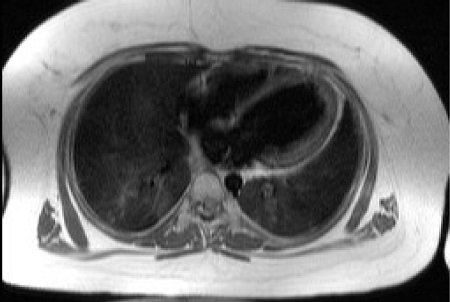

- Дилятационная кардиомиопатия с манифестацией в детском или подростковом периоде наблюдается более чем у 60 % случаев. На некоторых этапах жизни приводит к возникновению сердечной недостаточности и смерти. Обычно клиника дилятационной кардиомиопатии, и её результата — сердечной недостаточности зависит от возраста их проявления. Около 80 % больных переносят дилятационную кардиомиопатию в молодом возрасте. Из них 10 % имеют рецидивы, которые прогрессируют в более позднем возрасте.